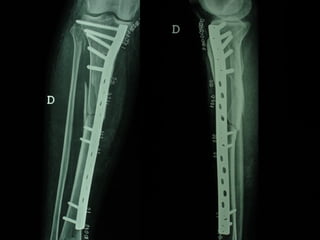

Dal Gennaio 2000 al Febbraio 2006 abbiamo trattato 167 fratture chiuse  con placca percutanea  in 164 pazienti :  27 lesioni diafisarie di gamba, 12 piloni tibiali ,  11 fratture prossimali di tibia, 36 fratture sovracondiloidee di femore, 17 fratture diafisarie di femore, 43 fratture metaepifisarie prossimali di omero, 21 diafisarie d’omero.  156 guarigioni 8 fallimenti

I buoni risultati ottenuti dipendono da 5 punti fondamentali:   una accurata riduzione percutanea della frattura  precise vie di accesso  l’utilizzo della placca che consenta il più lungo braccio di leva possibile il pretensionamento della placca  una sintesi con un ridotto numero di viti

VANTAGGI CHIRURGIA MININVASIVA Mini Open Inserimento della placca sottocutaneo per scivolamento Viti percutanee Preservazione dei tessuti molli Ridotto danno vascolare Rapida ripresa funzionale

LISS  NCB

NCB

Conclusioni Riduzione  anatomica Minimo trauma chirurgico Corretto equilibrio fra elasticità e stabilità Precoce mobilizzazione